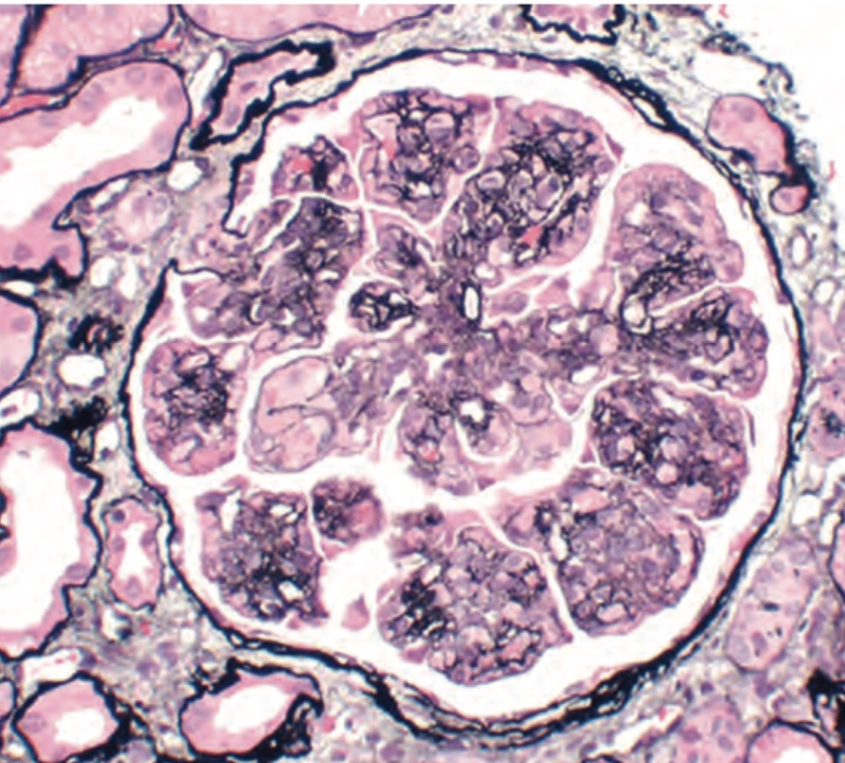

2) 조직학적 소견

① 광학현미경

Cresent 형성:

- Bowman's space에 epithelial parietal cell 증식

- 단핵구, 대식세포 침윤

- 세포층 사이에 섬유소(fibrin) 가닥이 뚜렷하게 관찰됨 (fibrinoid necrosis)

→ 진행 시 사구체 압박 및 폐쇄

Crescentic glomerulonephritis, Wikimedia Commons